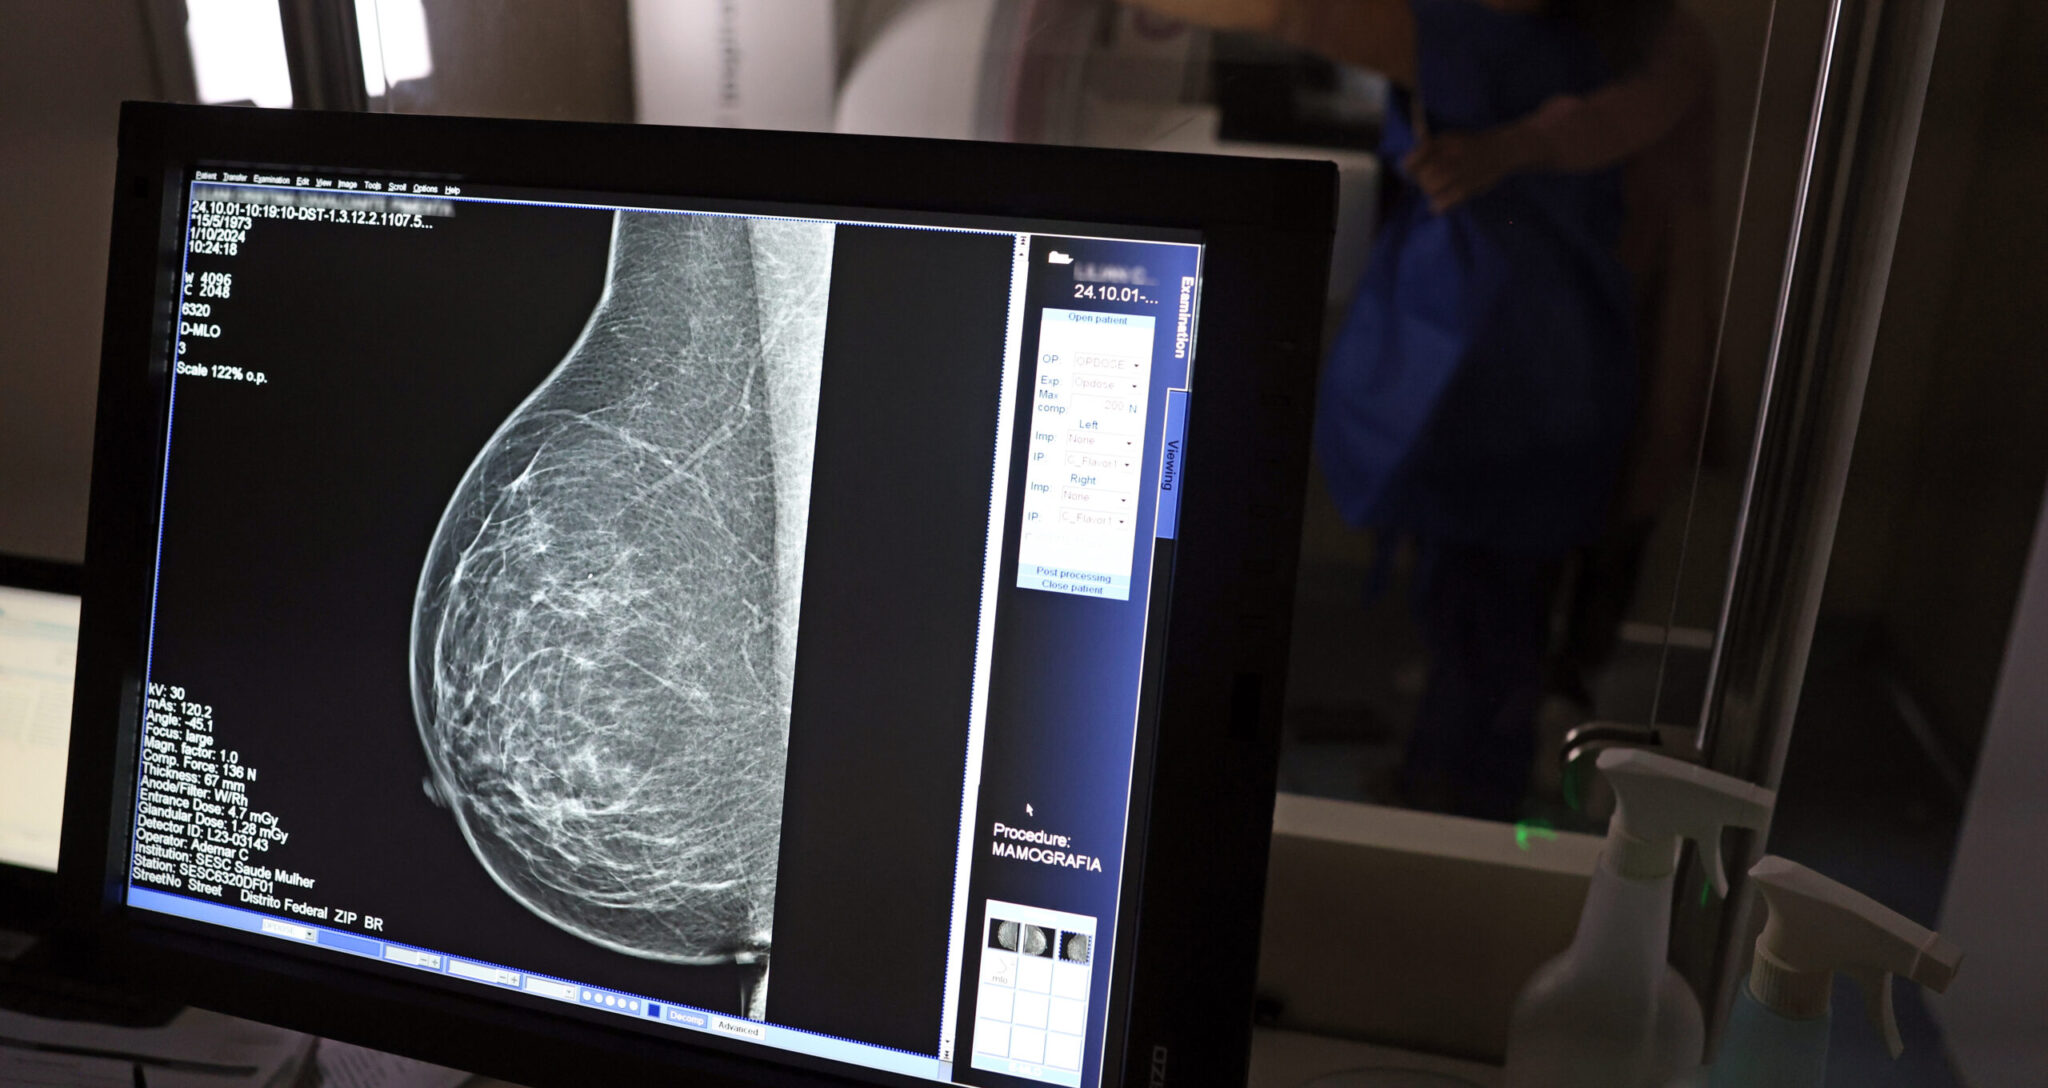

A rede estadual conta com 43 mamógrafos fixos e o serviço itinerante dos Caminhões da Mamografia, que percorrem os municípios levando o exame a quem mais precisa. O foco principal tem sido nas mulheres entre 40 e 49 anos, faixa etária que passou a ser atendida sob demanda, conforme nova orientação do Ministério da Saúde.

A técnica em radiologia Ana Vitória atua na Central de Diagnóstico de Valença e confirma o impacto direto na vida da população. “Antes o exame só era disponibilizado em clínica particular. Agora, mulheres de toda a região vêm aqui, fazem o agendamento e realizam o exame. Atendemos mulheres a partir dos 40 anos, sem fila, com estrutura pública. Isso melhorou muito a vida das pessoas”, afirma.